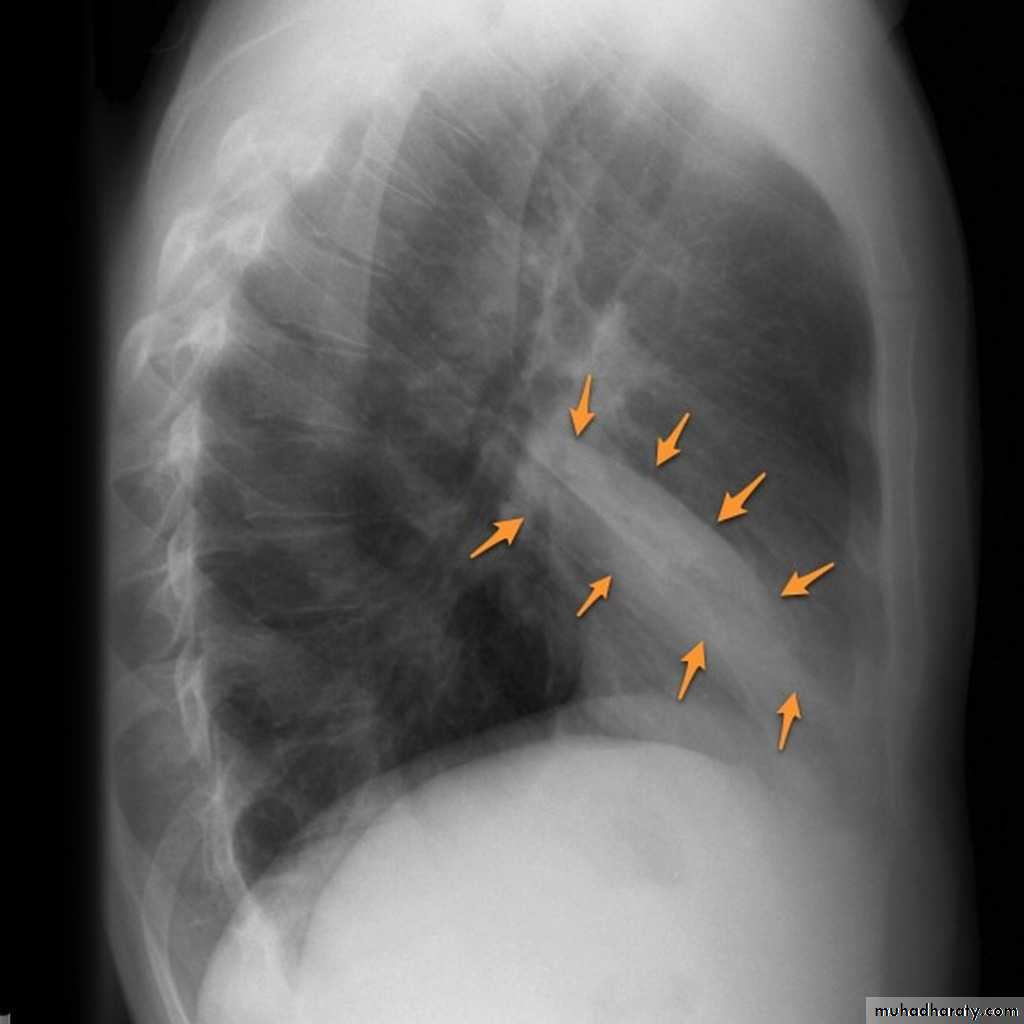

Left lower lobe collapse has distinctive features, and can be readily identified on frontal chest radiographs, provided attention is paid to the normal cardiomediastinal contours. The shadow cast by the heart does however make it harder to see than the right lower lobe collapse

Radiographic features

Left lower lobe collapseis readily identified in a well penetrated film of a patient with normal sized heart, but can be challenging in the typical patient with collapse, namely unwell patients, with portable (AP) often under-penetrated films, often with concomitant cardiomegaly. Features to be observed include :

triangular opacity in the posteromedial aspect of the left lung

edge of collapsed lung may create a 'double cardiac contour'

left hilum will be depressed

loss of the normal left hemidaphgragmatic outline

loss of the outline of the descending aorta

Non-specific signs indicating left sided atelectasis are usually also be present including:

elevation of the hemidiaphragm

crowding of the left sided ribs

shift of the mediastinum to the left

On lateral projection the left hemidiaphragmatic outline is lost posteriorly and the lower thoracic vertebrae appear denser than normal (they are usually more radiolucent than the upper vertebrae) .